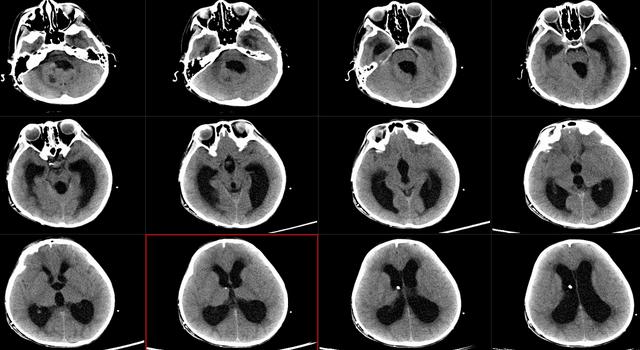

(图1 分流术后头颅CT,四脑室内占位,脑室系统扩张。)